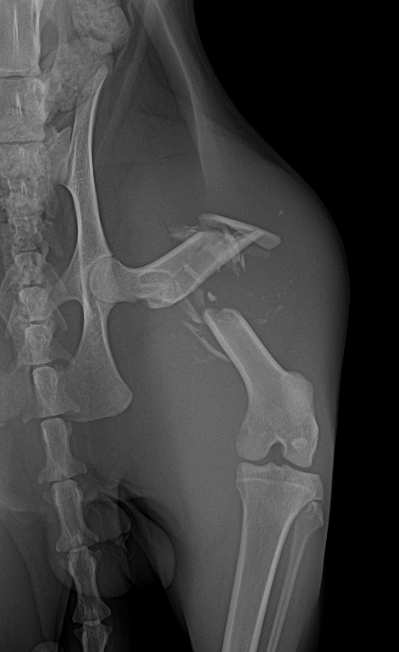

手術内容としては粉砕骨折の為、プレートとスクリューによる固定をしていただきました。

術後レントゲン画像

下記画像のような形で固定をしていただきました。